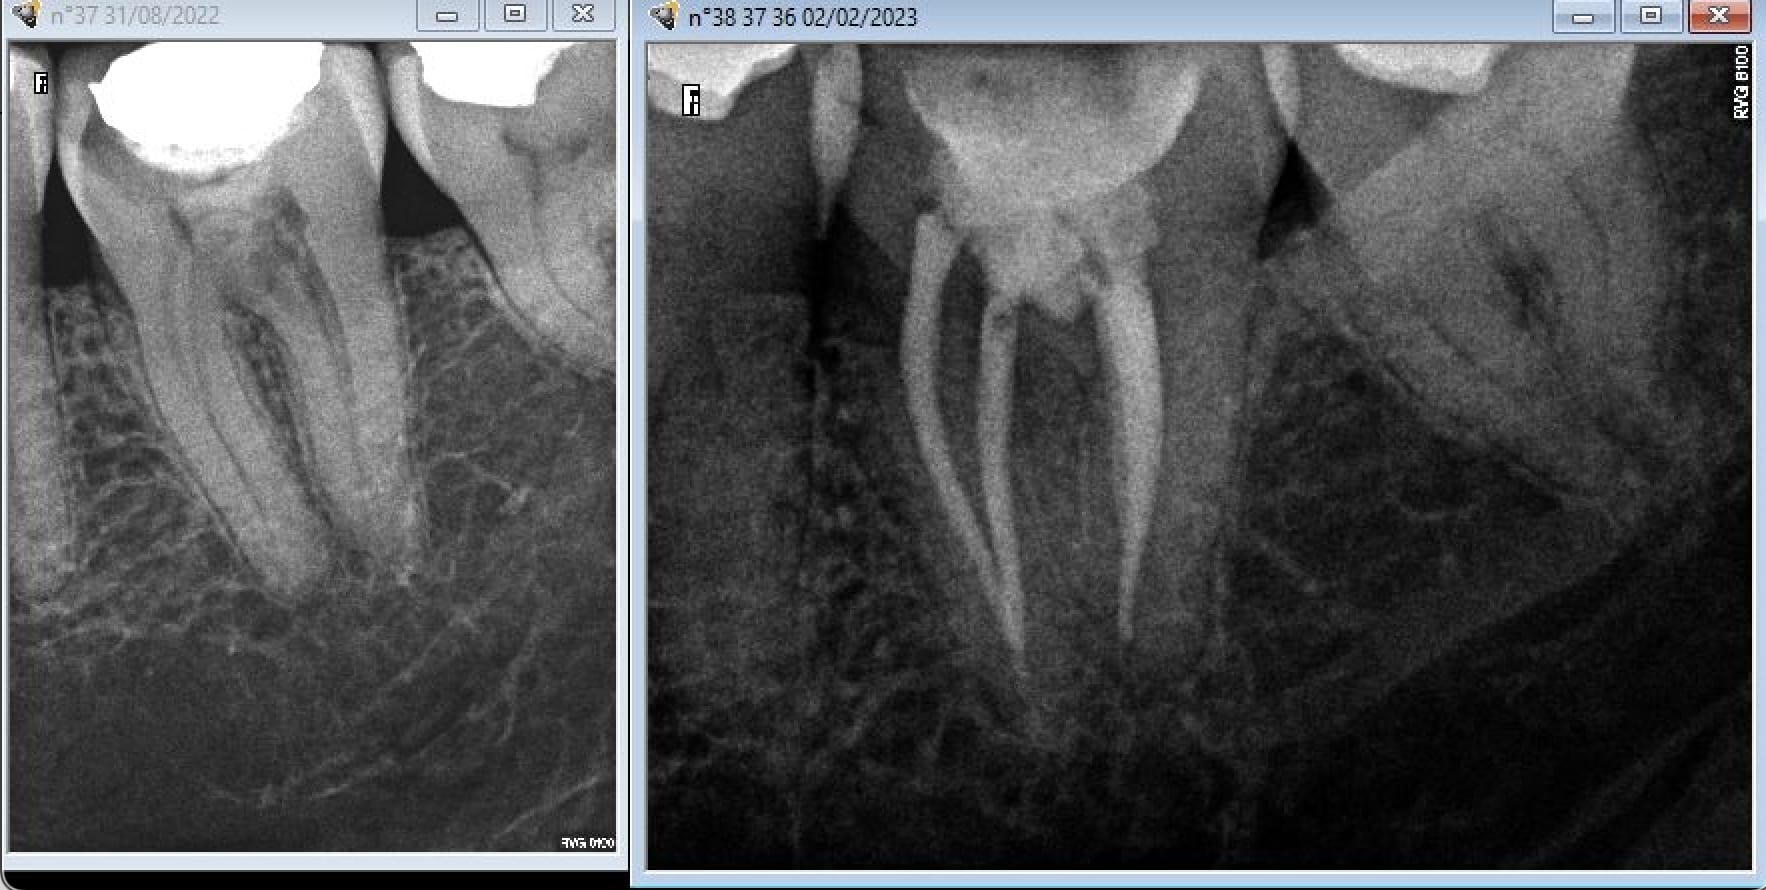

Tu peux faire ça aussi.

--

Ztazqvfo0icuajk94i1s5e4ijsx6 - Eugenol

Cherchez l'erreur.

Capteur.

Capture d  cran 2015 03 12 12.28 - Eugenol

Plaque . -)